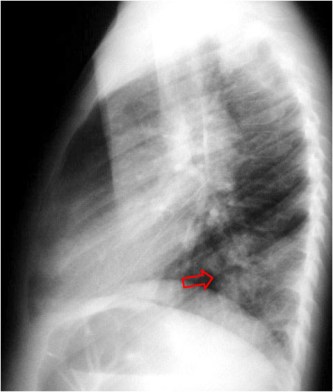

SIGNO DEL BRONQUIO 6

Este signo tiene el mismo significado que el signo del broncograma aéreo. La orientación del bronquio 6 (segmento apical del lóbulo inferior) hace que en vez de ver el broncograma como en otros lóbulos -dibujándose el trayecto bronquial- lo veamos de frente: sólo se ve una imagen redondeada de menor densidad que la consolidación (flecha).

La radiografía lateral confirma la localización en el segmento 6.